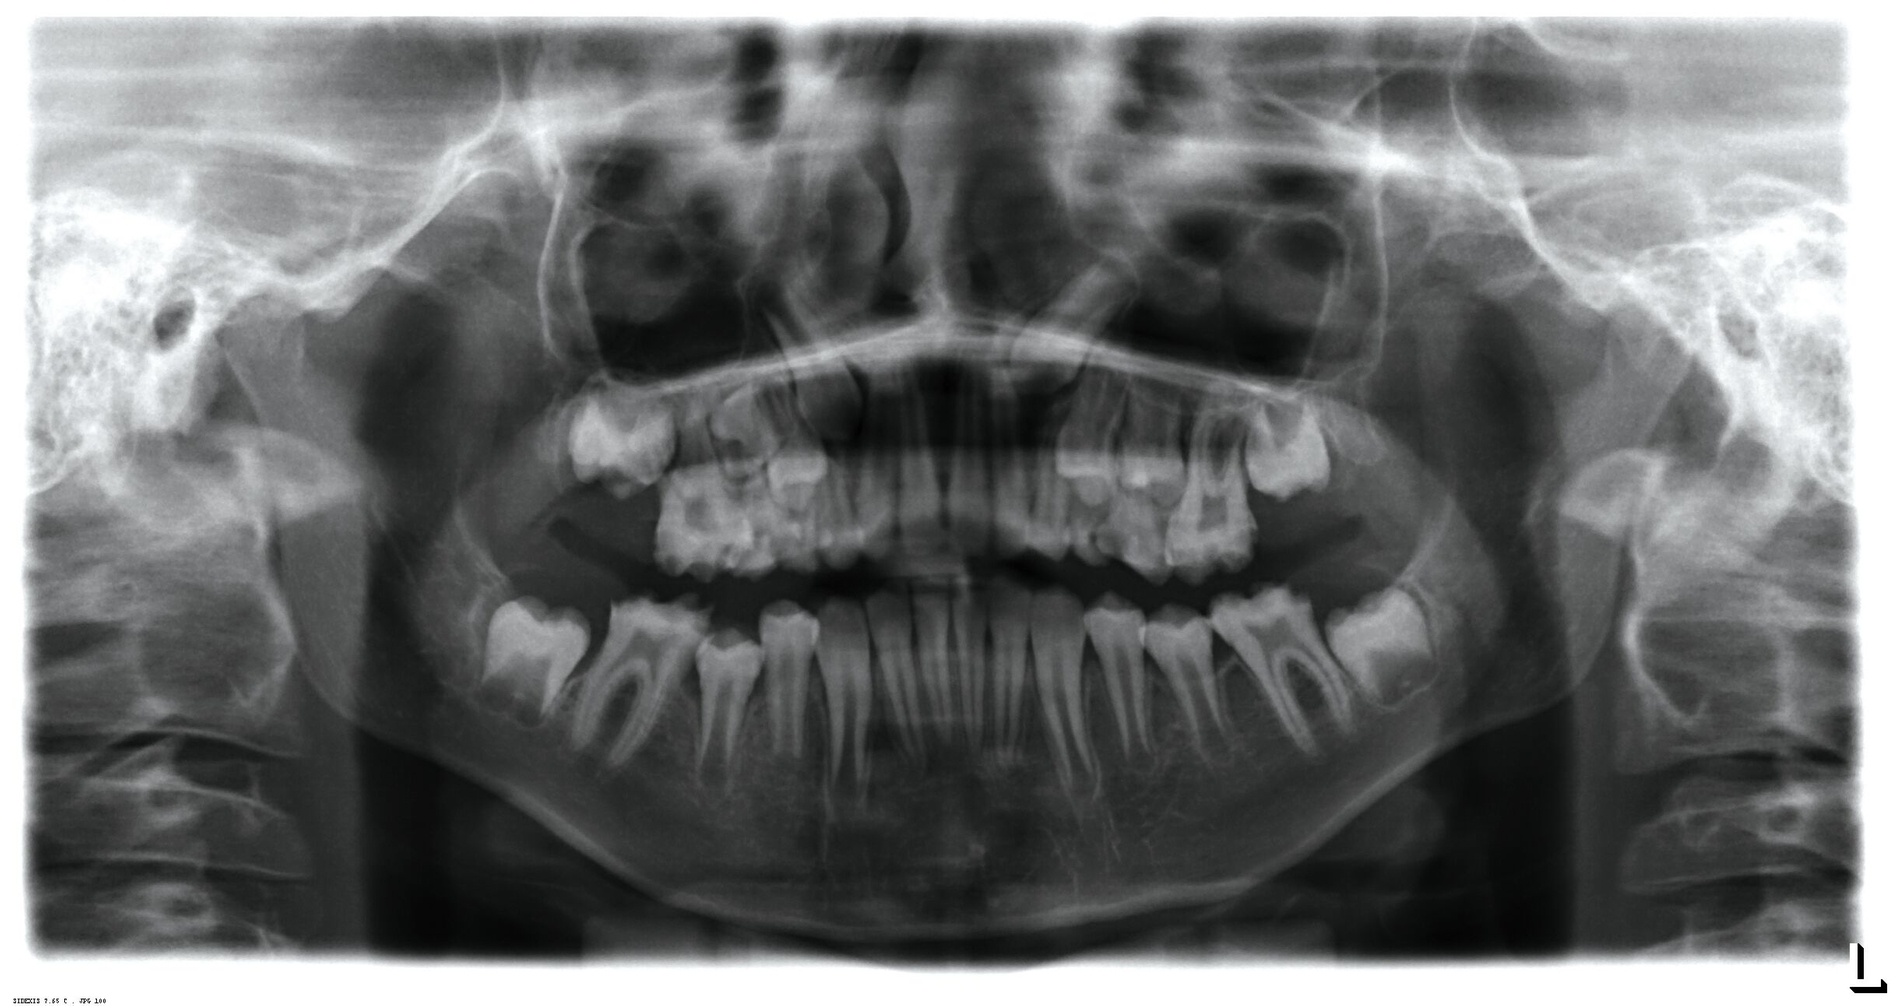

Klinisch zeigte sich ein kariöses Wechselgebiss mit generalisierten Verfärbungen und rauer Schmelzoberfläche. Mehrere Milch- und bleibende Zähne wiesen aktive kariöse Läsionen auf. Zahn 64 war zusätzlich druckdolent und gelockert, mit einer vestibulären Schwellung der Gingiva. Zudem bestanden eine Mittellinienabweichung, ein Overbite von vier Millimetern und ein Overjet von elf Millimetern (Abbildung 1). Extraoral fiel ein fliehendes Kinn mit inkomplettem Lippenschluss und hyperaktivem Musculus mentalis auf. Röntgenologisch waren alle Zähne angelegt, der Zahnschmelz zeigte jedoch eine reduzierte Opazität (Abbildung 2). Eine genetische Abklärung wurde von den Erziehungsberechtigten aus ethischen Gründen abgelehnt.